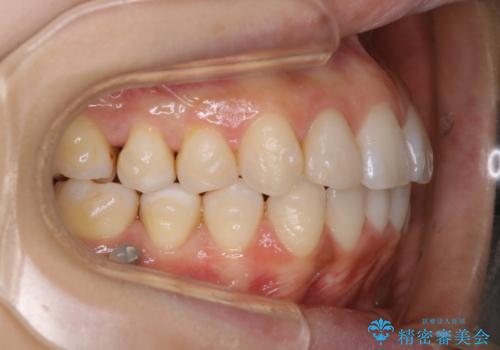

インビザラインの矯正中の方でアタッチメントが歯に付いているため、2ヶ月で着色やプラークが付いてきてしまいました。ホームケアや飲食の仕方により個人差はありますが、基本的には汚れが普段よりもつきやすいです。

定期的にクリーニングすることをおすすめします。